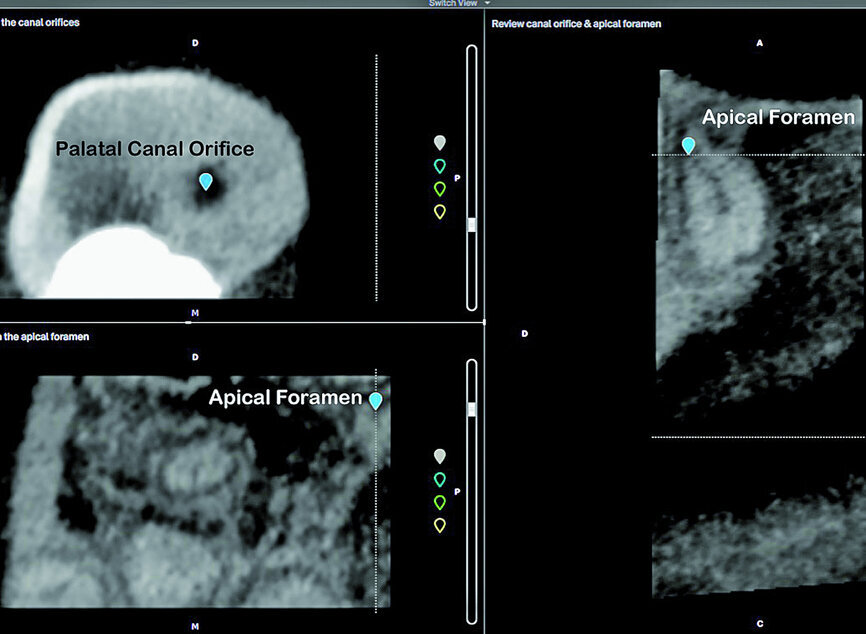

The second step, ‘3D Tooth Anatomy’, involved selecting the tooth to be examined and the entire volume was cropped to only leave the data of interest behind (Fig. 5). In the third step, ‘Canal System’, the number of root canals were identified and each root canal was then mapped separately by identifying the orifice and radiographic apical foramen of each root canal (Fig. 6).

Fig. 6: Identification of the palatal canal orifice and radiographic apical foramen.